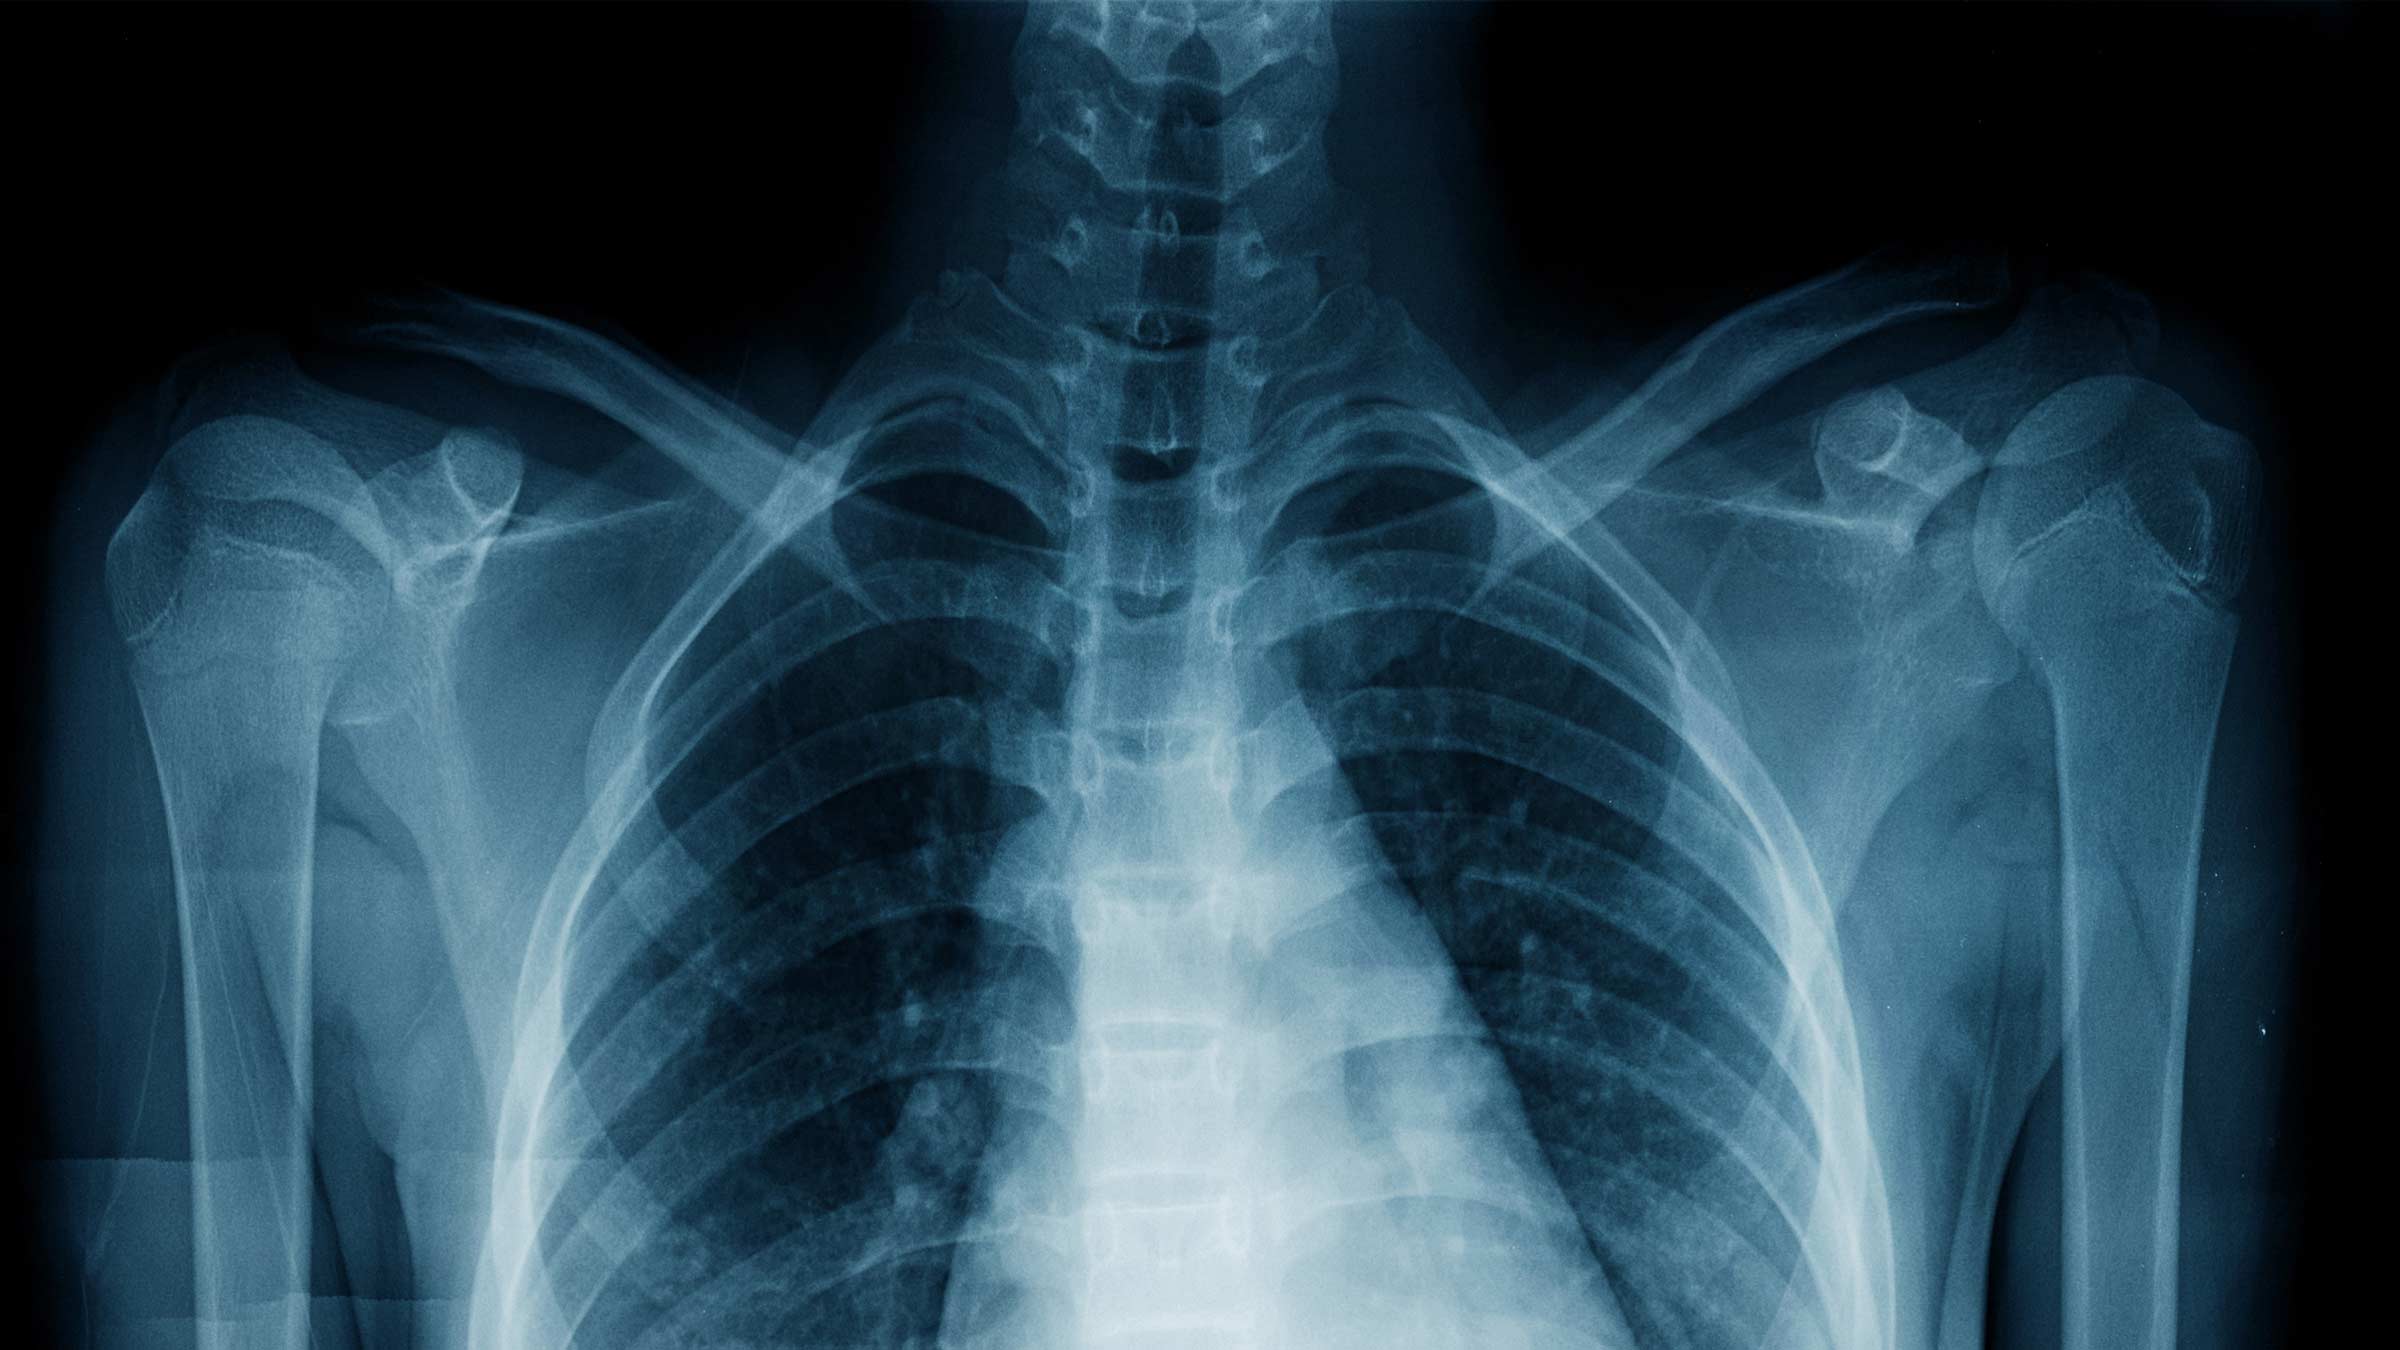

Xtray hotsell, X Rays Harvard Health hotsell

Product Name: Xtray hotsellX Ray What It Is What It Shows Preparation Types hotsell, X Ray BMD iHealth Centre Brampton Vaughan Rexdale Malton hotsell, X ray How it works strengths and limitations Spine Info hotsell, Digital X Rays Diagnostic Imaging Family First ER hotsell, Digital X ray Imaging Healthcare Specialists hotsell, Chest X Ray CXR What It Is What To Expect Results hotsell, How to interpret pelvic X rays 3 Essential Methods hotsell, X Ray South Coast Radiology hotsell, X Rays Harvard Health hotsell, Time for an X ray Evolution Imaging Technology News hotsell, X ray and what to expect Ohio State Health Discovery hotsell, What are X Rays Club Scientific hotsell, Diagnostic X Ray Imaging Services Northwest Radiology hotsell, True to Life Human X Rays Montessori Services hotsell, X Rays Johns Hopkins Medicine hotsell, X Ray Imaging BR P Radiologists hotsell, EOS Full Body Imaging What Is It Restore Function Physiotherapy hotsell, How to interpret hand X rays 3 Essential Methods hotsell, Puma X Ray Speed Trainers 38463848 Footballmania hotsell, How to read pelvic x rays International Emergency Medicine Education Project hotsell, What Do Chest X Rays Show hotsell, Smart X ray workflow helps reduce variability and imaging errors GE HealthCare United States hotsell, Suicide Mods X Orca Vape Stubby AIO X Ray Edition hotsell, Puma X Ray Speed Trainers 38463807 Footballmania hotsell, X Ray Chicago Diagnostic Imaging Techniques Chicago hotsell, Osteoarthritis Hip X Ray Findings Staging and More hotsell, Puma X Ray Speed Trainers 38463848 Footballmania hotsell, Difference Between an MRI and an X Ray SI Ortho hotsell, LADA X RAY 4WD NEUE LADA X RAY 4WD YouTube hotsell, Hand X Ray Anatomy Procedure What To Expect hotsell, General Radiography X rays Horizon Health Network hotsell, Suicide Mods X Orca Vape Stubby AIO X Ray Edition hotsell, Stubby AIO X RAY hotsell, How Long Do X Ray Results Take Can I Get My Report Online hotsell, Puma X Ray Speed Trainers 38463848 Footballmania hotsell.